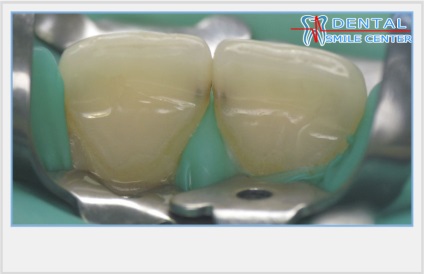

Felületi modellezés mátrix egy kivágás.

A késő 80-as és korai 90-es építettünk segítségével az érintkezési pontokat a mátrix a bevágás, mint megtudtuk abban az időben, hála nekik, az előadók a „Vivadentnél”. Performing helyreállítása, oly módon, kezdetben felújított központ és palatális felületre, majd beállítja a mátrix „csúcs” mind a felfekvő felületet és a fognyak és a zár a fogak közötti résekben impregnált ragasztó pamut golyó, helyreállított érintkező felületek. Szimulált helyreállítása befejeződött vestibularis felületének három részletben, hogy a készítményt a nyak és a központ vágóél, hogy szimulálja a színátmenetek és a vestibularis felületi bevonat réteg átlátszó árnyékot kompozit.

Ezen túlmenően, az érintkező felületek kellő mértékben sík. Azonban, ez a mátrix lehet alkalmazni egy vágott hasznosan nyitó poddesennoe helyet ellenőrzéshez vagy szigetelő bevonatot gingivális szélén a nyak a fog tömítőanyagot, például Force End Protect.